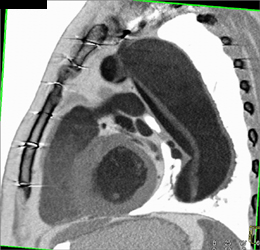

Type A Dissection